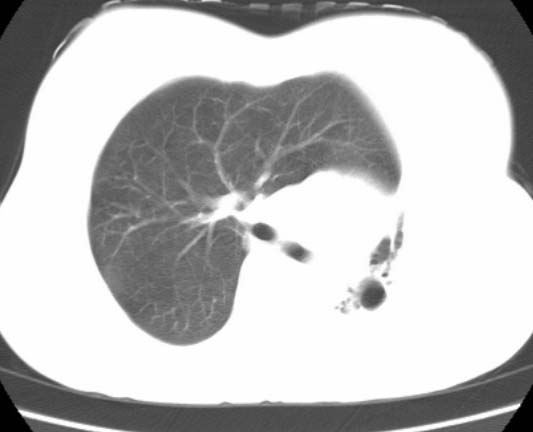

标题: CT25648:求教:是肺发育不全还是结核?

女  20岁。一月前咳血,诊“肺结核”抗痨治疗一月后,咳血停止,现复查。病人精神好。前后ct片对比未见明显变化。既往体检“正常”

1)考虑左肺结核并肺不张、支气管扩张。2)纵隔疝。

以前体检正常只能考虑左肺结核并肺不张、支气管扩张。2)纵隔疝。

考虑左肺结核,左肺毁损,纵膈左偏,既往体检正常不可靠,tb一个月也不会这个样子的,有钙化,应该病程较长,冰冻三尺非一日之寒!

考虑左肺结核,左肺毁损,纵膈左偏,既往体检正常不可靠,tb一个月也不会这个样子的,有钙化,应该病程较长,冰冻三尺非一日之寒

结核,左肺毁损。